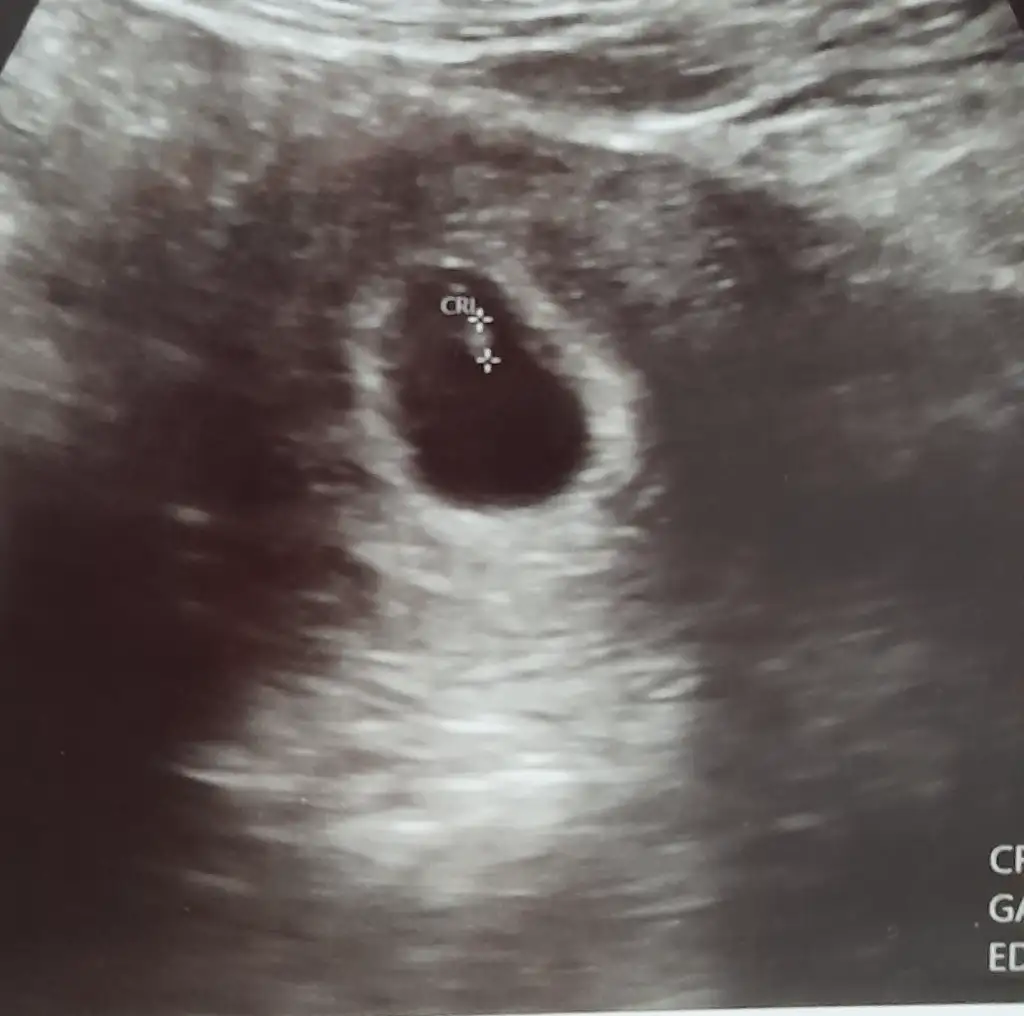

Amin Rabbim ikimizede erkek nasip eder o duyguyuda yatmayı nasip etsin inşallah sizin ultrason görüntüsü nasıl.bu arada bende 9 haftalık oldumRabbim gönlünüzdeki hayırlı versin inşallah. Benimde iki kızım inşallah benimde oğlum olur 7 haftalık gebeyim bende

Sizinkine benziyor fasulye gibi kese. Aminn inşallahAmin Rabbim ikimizede erkek nasip eder o duyguyuda yatmayı nasip etsin inşallah sizin ultrason görüntüsü nasıl.bu arada bende 9 haftalık oldum

Bu 6 haftalıkçok net göremiyorum ama içime kız doğdu

erkek gibi kesesi. benim oğlumun kesesi de böyleydiBu 6 haftalık